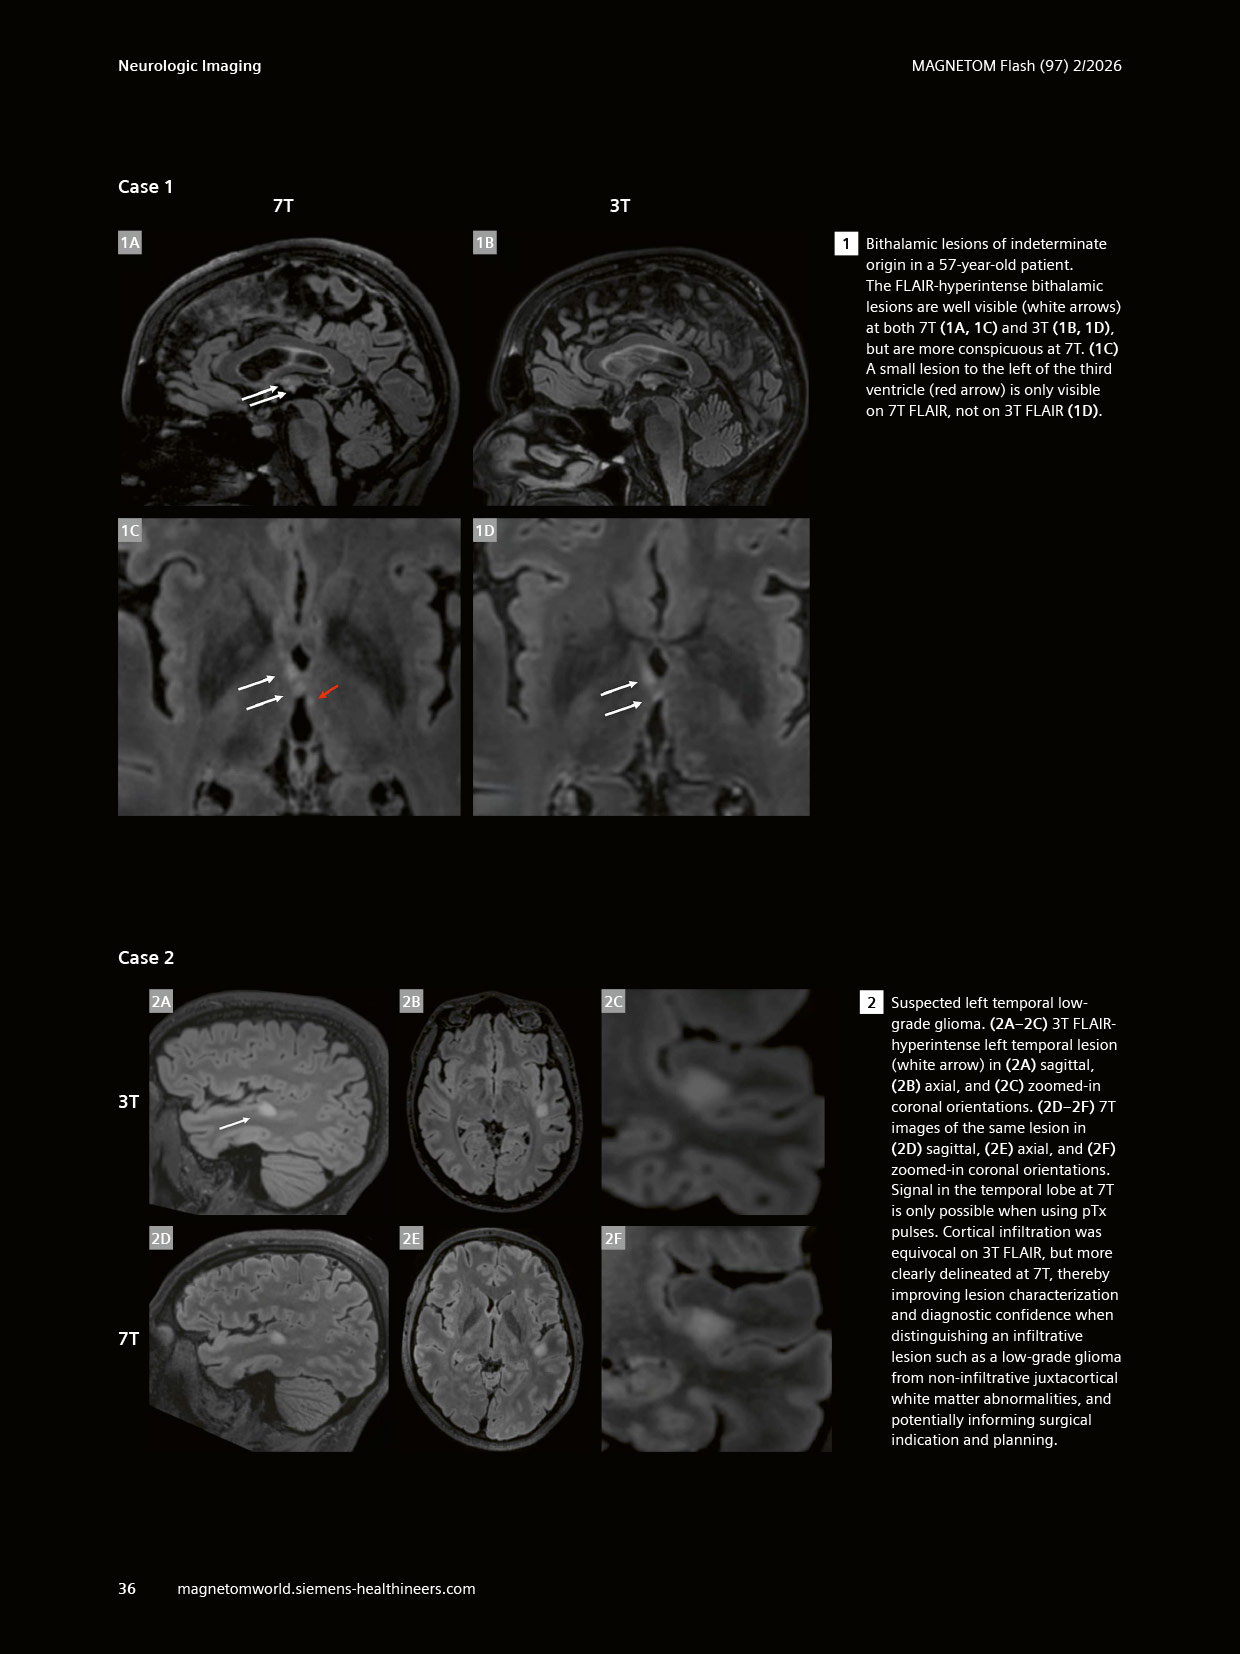

The article ” “Clinical Value of Optimized FLAIR Imaging at 7 Tesla: Neuroimaging Case Examples.” has been featured in MAGNETOM Flash, Issue 97 (2/2026, ISMRM Edition). Co-authored by Emilie Sleight, CIBM MRI EPFL Section and Fréderic Grouiller, CIBM MRI HUG UNIGE Section, Felix Kurtz, HUG, presents our continued commitment to advancing ultra-high-field MRI and its clinical translation.

The article highlights how optimised 7T FLAIR imaging enhances lesion detection and characterisation, with compelling clinical cases demonstrating its added value in neurological disorders such as multiple sclerosis and epilepsy. This work further underscores the growing role of 7T MRI in bridging cutting-edge research and clinical practice.